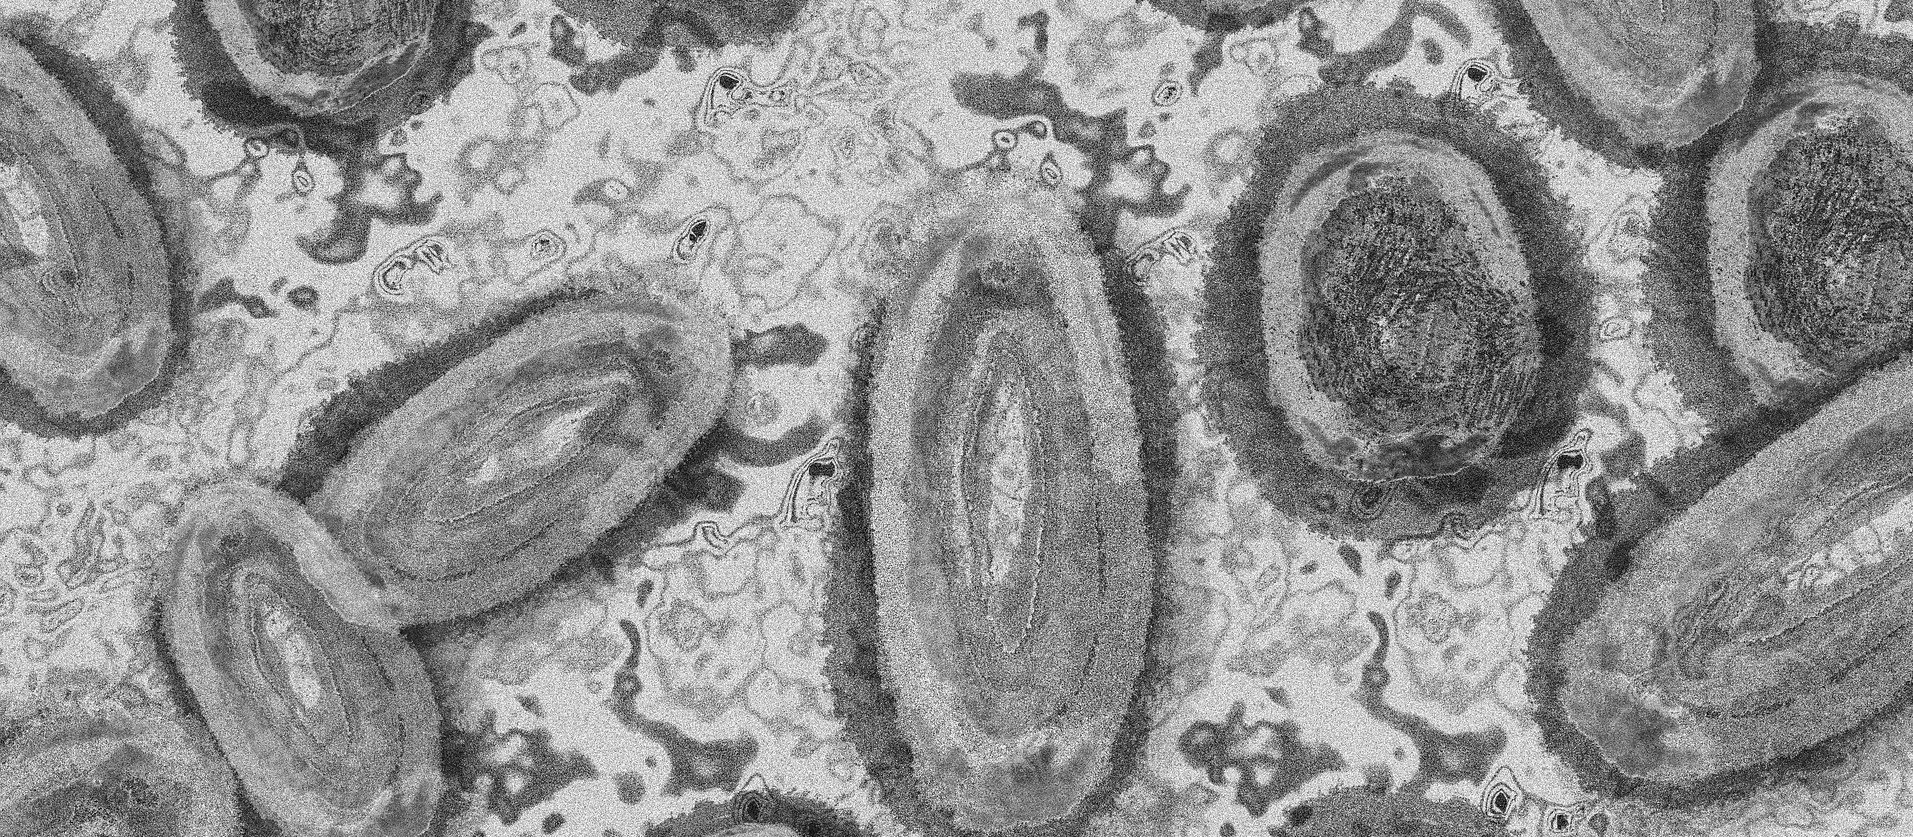

Imagem Ilustrativa/Representação abstrata do vírus da varíola/Gerd Altmann/Pixabay

O último caso confirmado no estado foi divulgado pela Secretaria Municipal de Saúde de Curitiba no último sábado (23).  Os sintomas causados pela Monkeypox, em uma primeira fase, são: febre, dor de cabeça, dores no corpo, calafrios e fadiga, que podem durar em média três dias. Já na segunda fase aparecem as lesões na pele. Além disso, nesse sábado (23) a Organização Mundial da Saúde (OMS) declarou que a varíola dos macacos é uma emergência mundial de saúde.